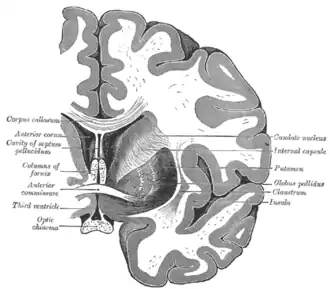

La commissure antérieure, appelée également la commissure blanche antérieure ou encore la précommissure (en latin : commissura anterior), est une commissure inter-hémisphérique qui croise transversalement la paroi antérieure du troisième ventricule[1]. C'est un faisceau nerveux de substance blanche (un paquet d'axones) qui relie les deux lobes temporaux des hémisphères cérébraux à travers la ligne médiane, et il se trouve en avant des colonnes du fornix (les piliers antérieurs trigone du cerveau). Chez la plupart des mammifères existants, la grande majorité des fibres reliant les deux hémisphères traversent le corps calleux, qui est plus de 10 fois plus grand que la commissure antérieure, et d'autres voies de communication passent par la commissure de l'hippocampe ou indirectement, via des connexions sous-corticales. Néanmoins, la commissure antérieure est une voie importante qui peut être distinguée clairement dans les cerveaux de tous les mammifères.

Dans une section sagittale, la commissure antérieure est de forme ovale, ayant un long axe vertical qui mesure environ 5mm.

Les fibres de la commissure antérieure peuvent être tracées latéralement et postérieurement de chaque côté au-dessous du corps strié vers la substance du lobe temporal.